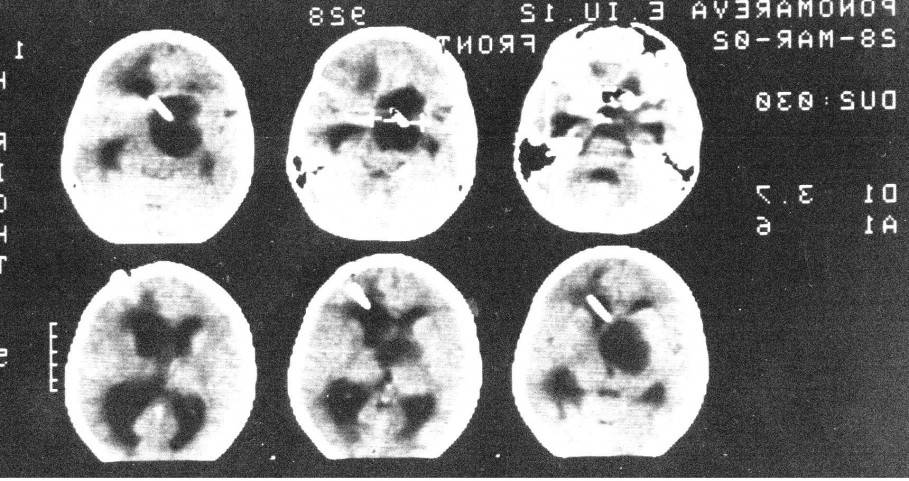

Отдельно хотелось бы остановиться на вмешательствах с использованием УЗ-навигации. Данный вид вмешательств относится к категории щадящих и малоинвазивных. При достаточной квалификации хирурга под УЗ контролем можно производить манипуляции с высокой точностью. Если ребенок грудного возраста, то датчик устанавливается на мембрану большого родничка. У старших детей датчик ставится на ТМО, для чего производится наложение трефинационного отверстия, часто и это не требуется, достаточно установить датчик на височную кость, которая даже у подростков сохраняет «прозрачность». Ниже пример осложненного течения гидроцефалии с т.н. изоляцией IV желудочка.

В этом случае УЗ-навигация позволила провести вентрикулярный катетер через отверстие Монро, III желудочек, провести реканализацию водопровода и провести его в IV желудочек, проведя т.о. Панвентрикулостомию: